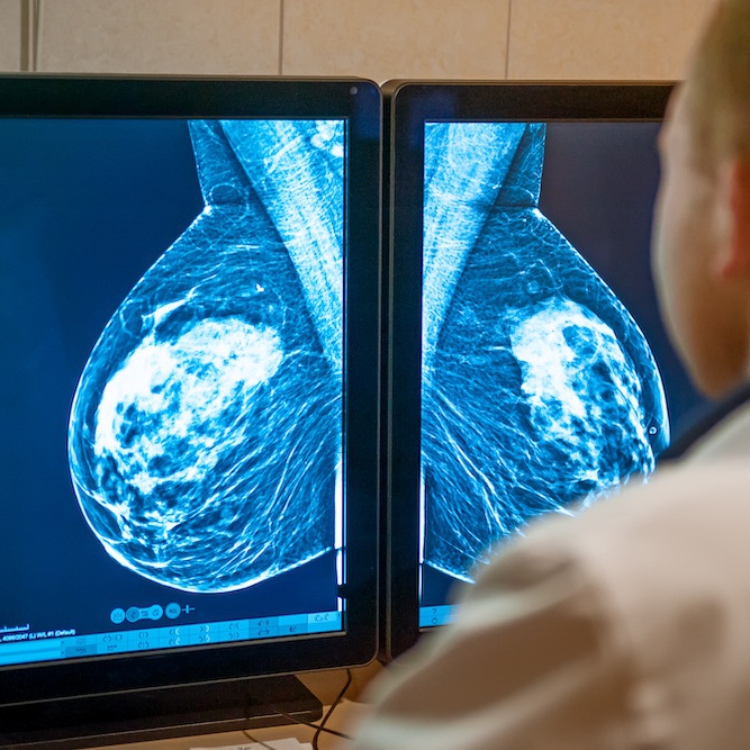

- ALIA Health, spin-off de TecSalud, y ÜMA Tech IA, Partner de Servicios de Google Cloud para el sector salud en Latinoamérica, desarrollan ALIA Health Risk Platform, una plataforma basada en inteligencia artificial que permite anticipar el riesgo de cáncer de mama a partir de mamografías.

En un contexto donde la mortalidad por cáncer de mama en México ha alcanzado uno de sus niveles más altos en décadas —con una tasa de 19.8 defunciones por cada 100 mil mujeres—, ALIA Health y ÜMA Tech IA anunciaron el desarrollo conjunto de ALIA Health Risk Platform, una plataforma basada en inteligencia artificial orientada a la predicción y estratificación del riesgo de cáncer de mama a cinco años, a partir de mamografías de la práctica clínica habitual.

Mammorisk+ es un modelo predictivo, entrenado con datos reales de práctica clínica y diseñado para estimar la probabilidad futura de desarrollar cáncer de mama en un horizonte de cinco años, exclusivamente en mujeres con mamografías sin hallazgos sospechosos. Su objetivo es actuar antes del diagnóstico, en la etapa donde se definen estrategias de prevención, seguimiento y personalización del tamizaje.